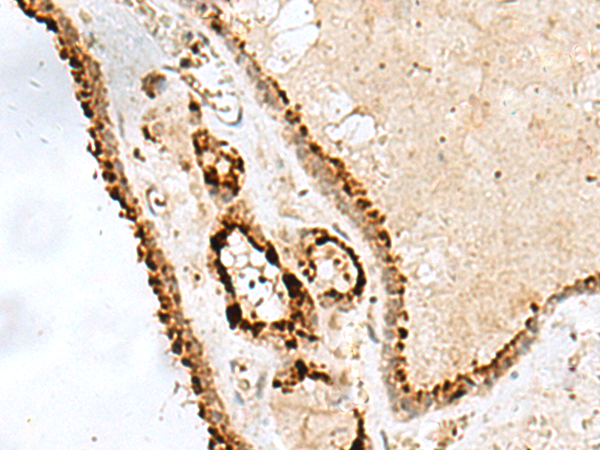

IHC positive control: |

Human thyroid cancer |

IHC Recommend dilution: |

20-100 |